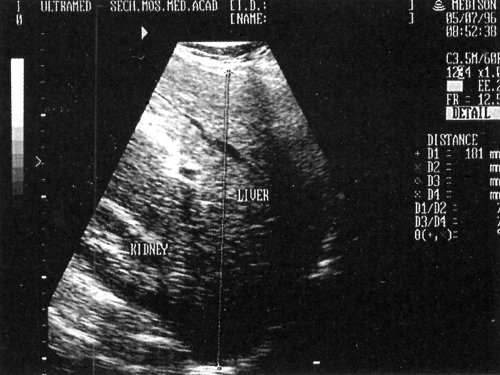

Рис. 4. Эхограмма правой доли печени при ее увеличении: Liver - печень, Kidney - почка.